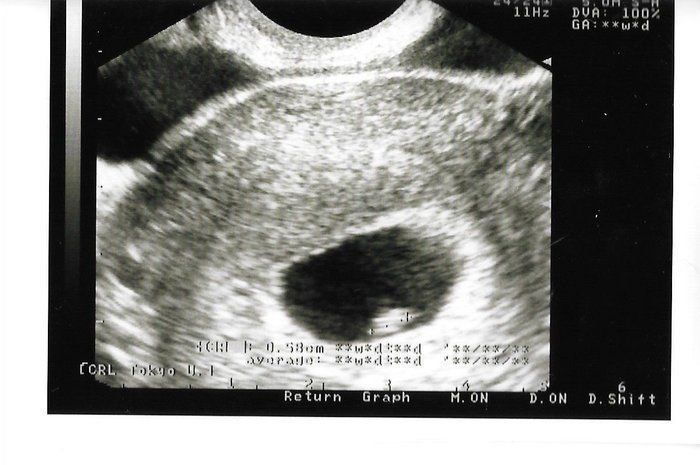

なつさんの妊娠6週目のエコー写真

妊娠発覚!2ミリくらいですと言われる。

転職活動中、「そういえば生理が来てないな。もしかして」と思い、レディースクリニックに行きました。診察してみると妊娠しており、すでに6週でした。子どもは将来いずれと思っていましたが、結婚もまだまだ先のことだと思っていたので心の準備が全くできておらず、正直ショックで「どうしよう」と思いました。呆然としながらもエコー写真を見てだんだん産みたいという決心がついてきました。